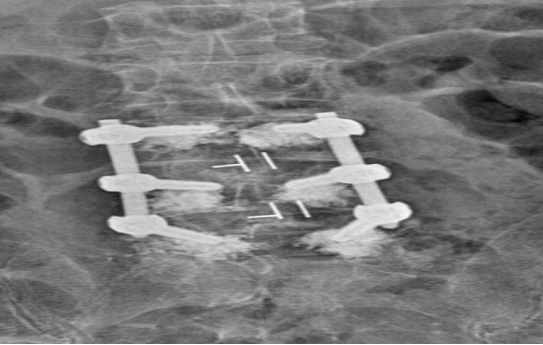

術(shù)中�����,團(tuán)隊(duì)采用先進(jìn)的骨水泥椎體強(qiáng)化技術(shù)�,有效解決了骨質(zhì)疏松導(dǎo)致的螺釘固定難題。在麻醉團(tuán)隊(duì)的精密護(hù)航下�,手術(shù)全程僅用時(shí)2小時(shí),出血量不足100ml����。術(shù)后護(hù)理團(tuán)隊(duì)實(shí)施ERAS快速康復(fù)方案,通過疼痛管理��、早期康復(fù)訓(xùn)練等舉措�����,幫助老人在術(shù)后第5天即可自主行走。

作為區(qū)域脊柱外科診療中心��,衡陽市中心醫(yī)院脊柱外科創(chuàng)新開展了“椎體強(qiáng)化聯(lián)合椎弓根螺釘固定”技術(shù)�,已為百余例高齡患者成功實(shí)施手術(shù)��。此次手術(shù)的成功�,體現(xiàn)了醫(yī)院多學(xué)科協(xié)作的優(yōu)勢,更彰顯了醫(yī)療團(tuán)隊(duì)精湛的技術(shù)�。